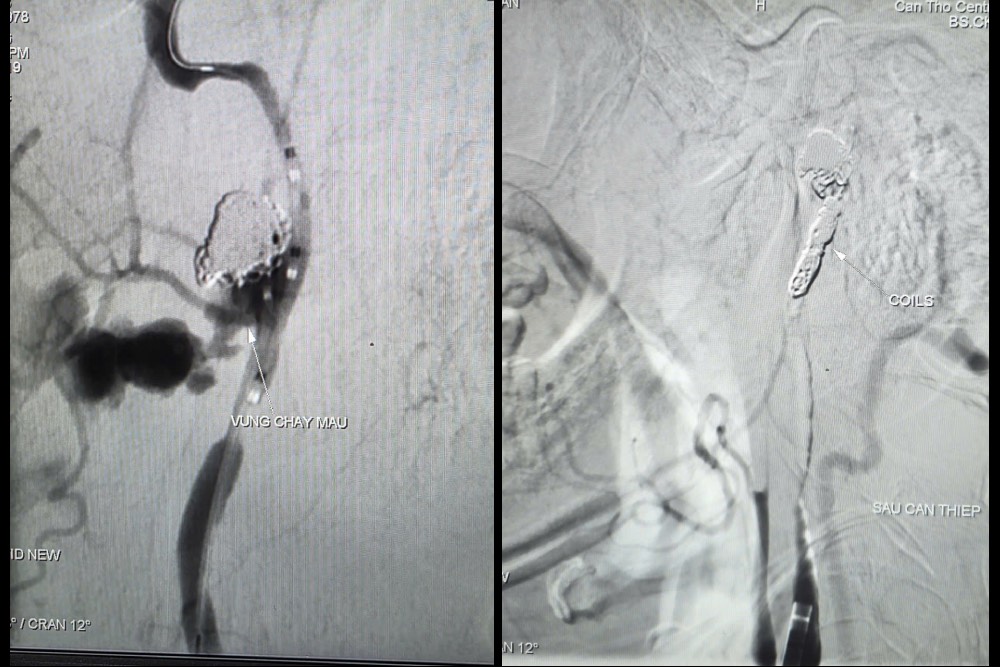

Trước tình huống nguy kịch, các bác sĩ quyết định thực hiện chụp và can thiệp cầm máu dưới mạch số hóa xóa nền (DSA). Kết quả ghi nhận ổ giả phình động mạch cảnh trong phải đoạn cổ, dưới nền sọ, kích thước 4,2 x 4,8 mm, cổ túi phình rộng và đang chảy máu.

Các bác sĩ đã bóng chẹn dòng chảy kiểm soát lượng máu chảy ra từ túi phình và tiếp tục luồn vi ống thông (ống thông siêu nhỏ) chọn lọc đến vị trí túi phình và tiến hành thả 09 vòng xoắn kim loại (coils) để gây tắc hoàn toàn ổ giả phình và động mạch cảnh trong phải, nhằm kiểm soát triệt để nguồn chảy máu. Chụp kiểm tra từ động mạch cảnh trong trái cho thấy có tuần hoàn bàng hệ nuôi bán cầu não phải qua động mạch thông trước, đảm bảo tưới máu não sau can thiệp.